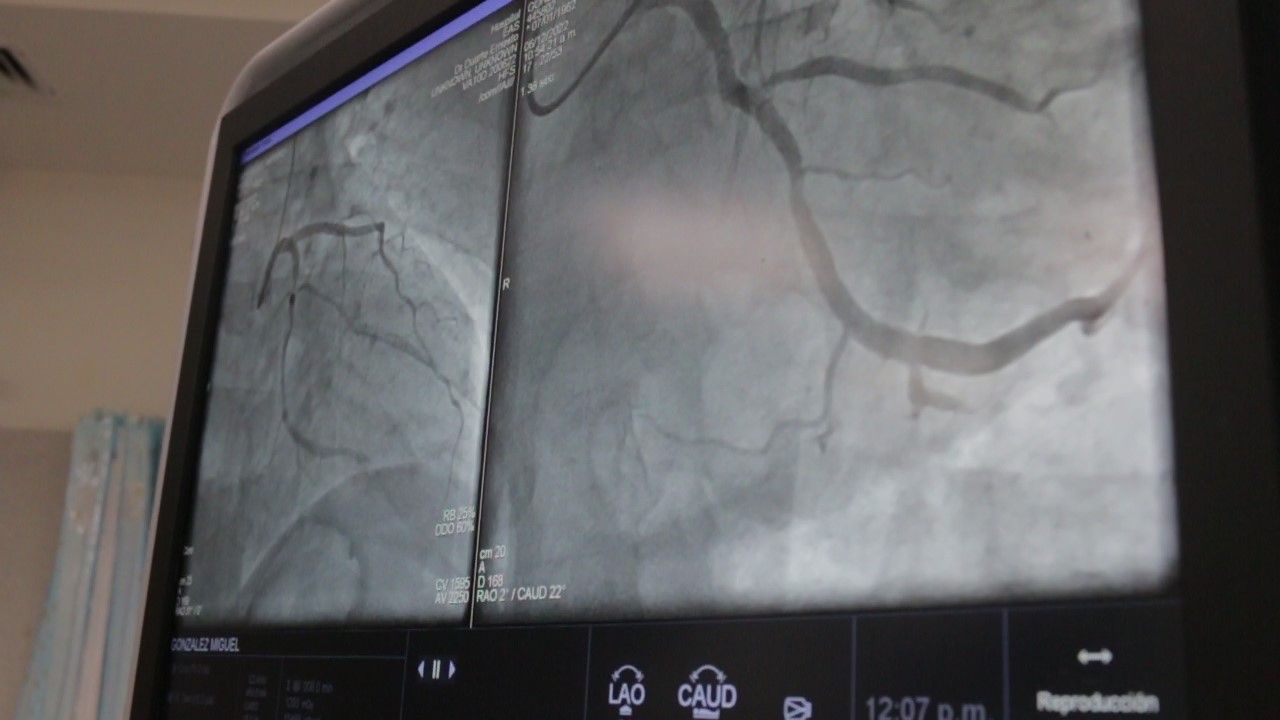

Para resolverlo, el equipo utilizó por primera vez en el hospital el dispositivo Clotriver. “Es un dispositivo que pasa a través de la vena que está trombosada, extrae los trombos, podemos observar en las imágenes, trombos frescos o trombos un poco diferentes, de diferentes días de evolución y se los puede traer a todos los trombos y recanalizar y mejorar nuevamente el flujo”, explicó el especialista.

El mecanismo es preciso: “Tiene una canasta que captura todo lo que es trombo que está detenido en la vena ilíaca y poder extraerla en forma total o casi total. Finalmente se coloca un stent en el sector donde está afectada la vena ilíaca y obviamente esa es la conclusión o finalización del tratamiento con la permeabilidad o repermeabilización de la vena hacia el torrente circulatorio”.